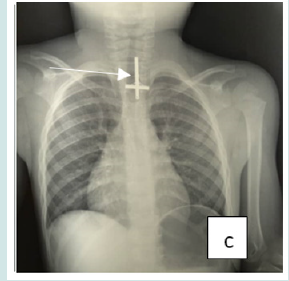

Cervico-thoracic X-ray performed in 211 cases (99%) showed opacity in 209 cases (99%). In one case, 2 circular opacities were observed, one of which had a double contour, indicating the ingestion of 2 foreign bodies (Figure 1: a, b, c, d, e, f). Foreign objects were a coin in 182 cases (85.4%), a shirt button in 4 cases (1.88%), a food in 7 cases (3.27%), and a flat battery in 3 cases (1.41%) (Table III). In 2 cases (1%) the EC was radiolucent.

Figure 1: Front cervico-thoracic radiograph showing different radiopaque foreign bodies (a,b,c,d,e,f). a: Circular esophageal CE of metallic tone, round opacity (coin).